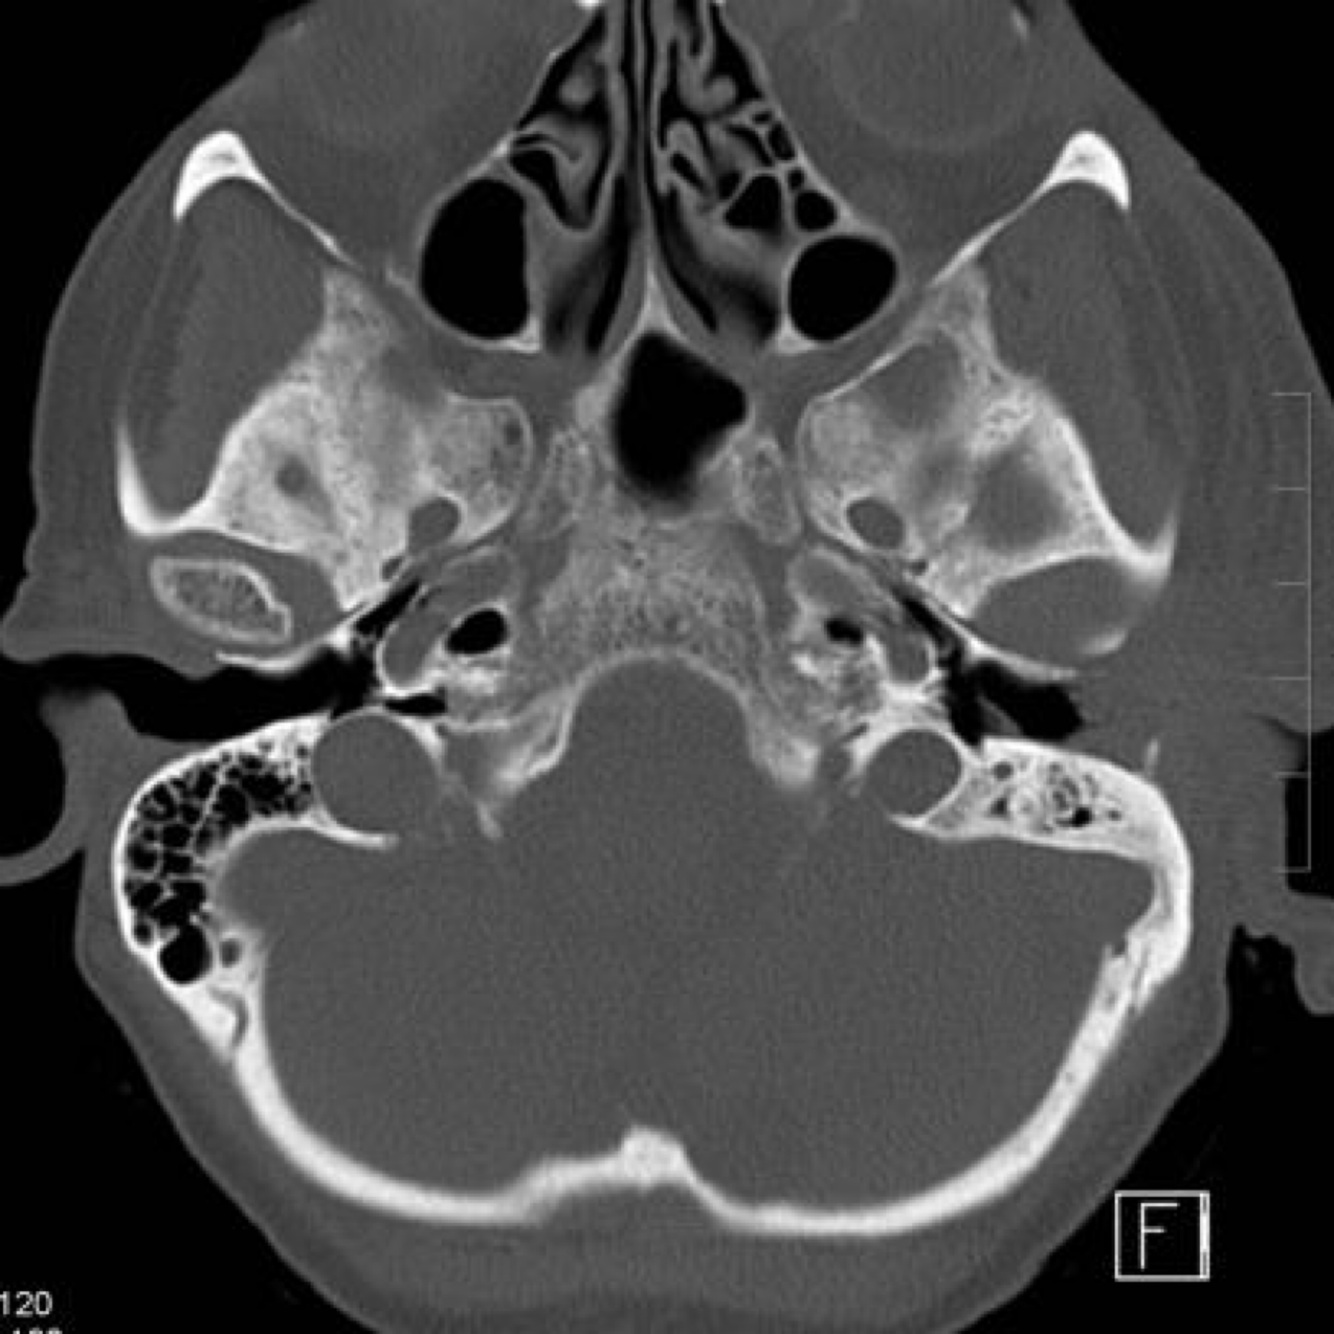

In a patient with atresia of the EAC, the FN tends to be dehiscent in the ___ segment and can overlie the ___.

In a patient with atresia of the EAC, the FN tends to be dehiscent in the tympanic segment and can overlie the oval window.